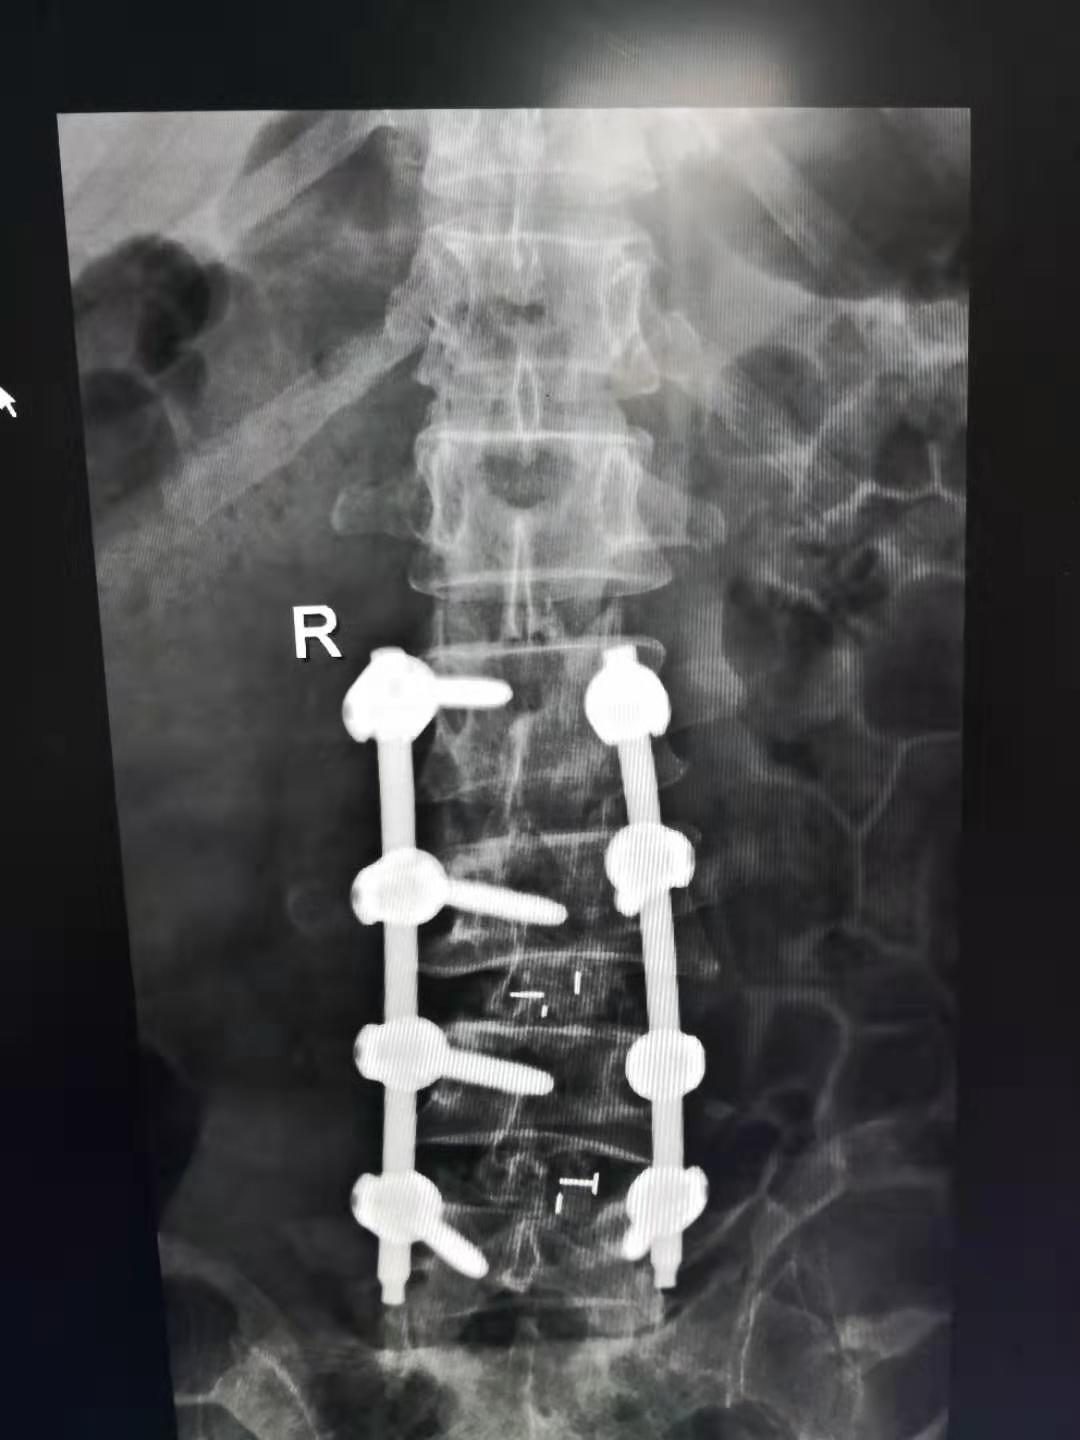

经过完善的术前准备后,为患者在全麻下行腰椎L2-L5侧凸矫形、L3/4 L4/5经椎间孔入路椎间盘切除椎体间植骨融合、L2/3后路关节突关节成形植骨融合L2-L5RSS内固定术,手术由侯卫涛副主任医师、常乐主治医师配合,历时3个半小时,顺利完成。

术后患者X片